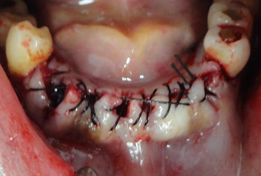

Os alvéolos, preservados, durante as extrações, foram preenchidos com Hemospon (Esponja Hemostática de Colágeno Hidrolisado (Gelatina) liofilizada). Suturados firmemente, espera- de 15 a 30 minutos para que a gelatina do Hemospon, induza a formação de fibrina, formando o coágulo, no defeito ósseo. Que através de histodiferenciações celulares, que descreveremos, induzirá a formação óssea.